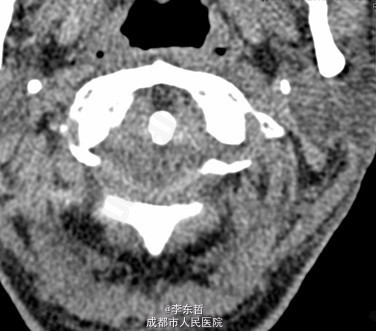

陈旧性寰枢关节脱位

患者男性,54岁,因“外伤后头颈部疼痛2年加重伴活动受限1个月”入院,自诉疼痛呈慢性起病,间歇性、反复发作并逐渐加重,为求进一步诊治故来我院,门诊以“陈旧性寰枢关节脱位”收入我科。